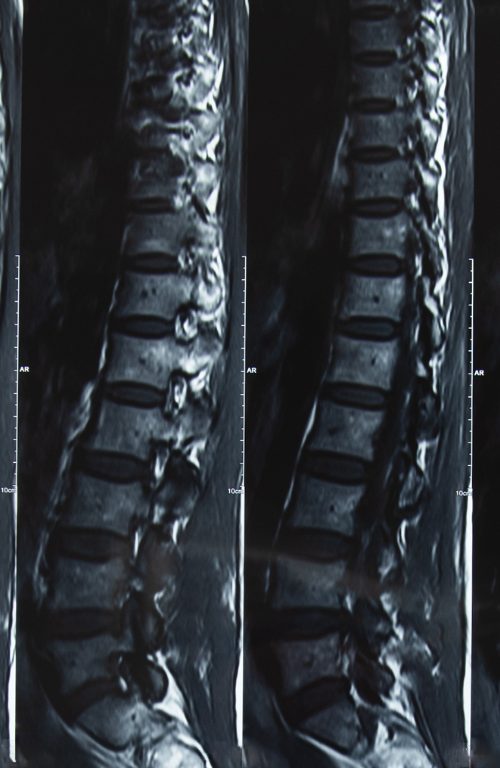

Annulogram and Not MRI, is What the Doctor Ordered for Low Back Pain

Nashville Medical News takes a look at why an Annulargram™ is a better option for diagnosing back pain than MRI. Read the article here.Get your no-obligation, free consultation to learn more about…